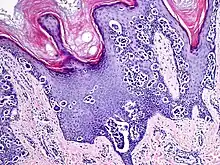

Additional image